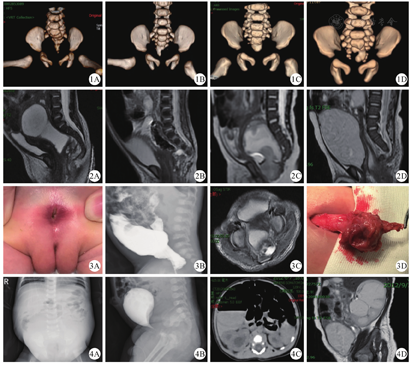

例1:患儿,女,15 d,因"进行性腹胀1周"入院。体格检查:腹胀明显,腹壁静脉怒张,肛门开口狭窄,仅能通过9号扩肛器。碘水造影提示直肠肛门狭窄,CT重建示尾椎侧曲畸形,偏向右侧(图1A),磁共振成像(magnetic resonance imaging,MRI)检查证实骶前稍偏左侧有混杂信号肿块,多考虑为畸胎瘤(图2A)。行后矢状路径骶尾部畸胎瘤切除术+直肠拖出瘘管切除术+肛门成形术,术中在骶前肿物内见脂质及毛发,并可见骶前有清亮似脑脊液物质流出,考虑有脊膜膨出,予以5-0 PDS线修补(图3)。病理诊断为成熟畸胎瘤,包块内可见神经组织。术后3 d拔出尿管,不能自行排尿,复查腹部X线正位片提示腹腔积液待排(图4A)。予以导尿,一次性引流出黄色清亮尿液710.0 ml。早期持续导尿,后期训练膀胱功能,3个月后能自行排尿,B型超声提示膀胱残余尿量为55.5 ml。1岁行MRI复查提示左侧输尿管扩张,截面大小为0.9 cm×1.2 cm。目前诊断为神经源性膀胱。现间断导尿,6次/d,并有便秘,需开塞露塞肛才有大便排出。

例2:患儿,女,17 d,因"腹胀5 d,呕吐1 d"入院。体格检查:腹平,肌软,肛门狭窄,仅6号扩肛器可通过。碘水造影提示直肠肛门狭窄,瘘管长约3 cm,CT重建示骶尾椎发育异常(图1B),MRI检查于骶前可见包块,考虑骶前脊髓脊膜膨出,脊髓栓系(图2B)。入院后行乙状结肠造瘘术,于3个月后行后矢状路骶尾部包块切除术+脊髓栓系松解术+直肠拖出瘘管切除术+肛门成形术。术中见包块与骶前粗大终丝和粘连成束的神经根相连,切除骶前包块,松解栓系,修补硬脊膜。病理诊断为成熟畸胎瘤,脊髓栓系。术后2 d拔出尿管,尿道口无尿液排出,B型超声提示膀胱充盈明显,予以导尿,早期持续导尿,后期间断2~3 h夹闭尿管,训练膀胱功能,2个月后膀胱功能恢复,能自行排尿,B型超声提示膀胱残余尿量约为18.5 ml。随访1年,泌尿系统未见异常。

例3:患儿,男,3 d,因"出生后发现无肛门开口3 d"入院。体格检查:腹胀明显,腹肌软,肛隐窝处未见正常肛门开口,未见瘘口,尿道口未见大便排出。入院后行倒立位X线片示高位肛门闭锁,CT重建示尾椎缺失,骶椎形态不规则(图1C),入院后行结肠暂时性造口术,术后2个月突然出现无尿,行MRI及逆行性膀胱造影检查发现骶前肿物压迫膀胱,行后矢状路径骶尾部肿物切除术+直肠脱出肛门成形术,术后3 d拔除尿管后能自行排尿,术后1个月行逆行性膀胱造影检查提示膀胱残余尿量约为6.5 ml。病理诊断为成熟畸胎瘤。术后随访3年,无排尿异常。

例4:患儿,男,8 h,因"出生后发现无正常肛门开口8 h"入院。体格检查:肛隐窝处未见正常肛门开口,于出生后24 h行倒立位X线片提示高位肛门闭锁,腹部CT检查提示尾椎缺如,骶椎形态不规则(图1D),并可见双侧肾盂扩张,右侧为重,但漏诊骶前包块(图4C)。行暂时性结肠造口术,3个月龄时行Peña手术,术中发现骶前囊实性包块,大小约为30 mm×30 mm×30 mm,同时予以切除。病理诊断为畸胎瘤。术后拔除尿管可自行排尿。术后1个月行MRI检查发现双肾积水,膀胱扩张,右侧肾积水较左侧重(图4D),后期失访。

4例新生儿Currarino综合征患儿均出现尿潴留:例1和例2为切除骶前包块及直肠拖出瘘管切除及肛门成形术后出现尿潴留。例1在术后3个月虽能自行排尿,1年后复查仍有输尿管扩张,考虑神经源性膀胱,现每日清洁导尿,并出现便秘情况,需每日清洁灌肠,复查钡剂灌肠提示乙状结肠扩张,直肠稍显狭窄,肛门直肠测压可见肛门抑制反射(反射阈值为30 ml),刺激前后肛门蠕动幅度低浅,节律性差。乙酰胆碱酯酶阳性,神经纤维阴性。例2于2个月后恢复排尿功能,术后随访1年,现排便、排尿正常。例3为骶前畸胎瘤压迫导致泌尿系统机械性梗阻(图2C),切除瘤体后短期内尿潴留缓解,术后排便、排尿正常。例4为先天性肛门闭锁(高位),出生后行CT检查即发现肾积水,于二期行Peña术,术中发现骶前包块,术后复查MRI,骶前包块消失,双肾积水较前加重,肾实质变薄,呈花边状,以右侧明显,膀胱体积增大(图4D),后期失访。所有患儿均未出现双下肢活动功能障碍。